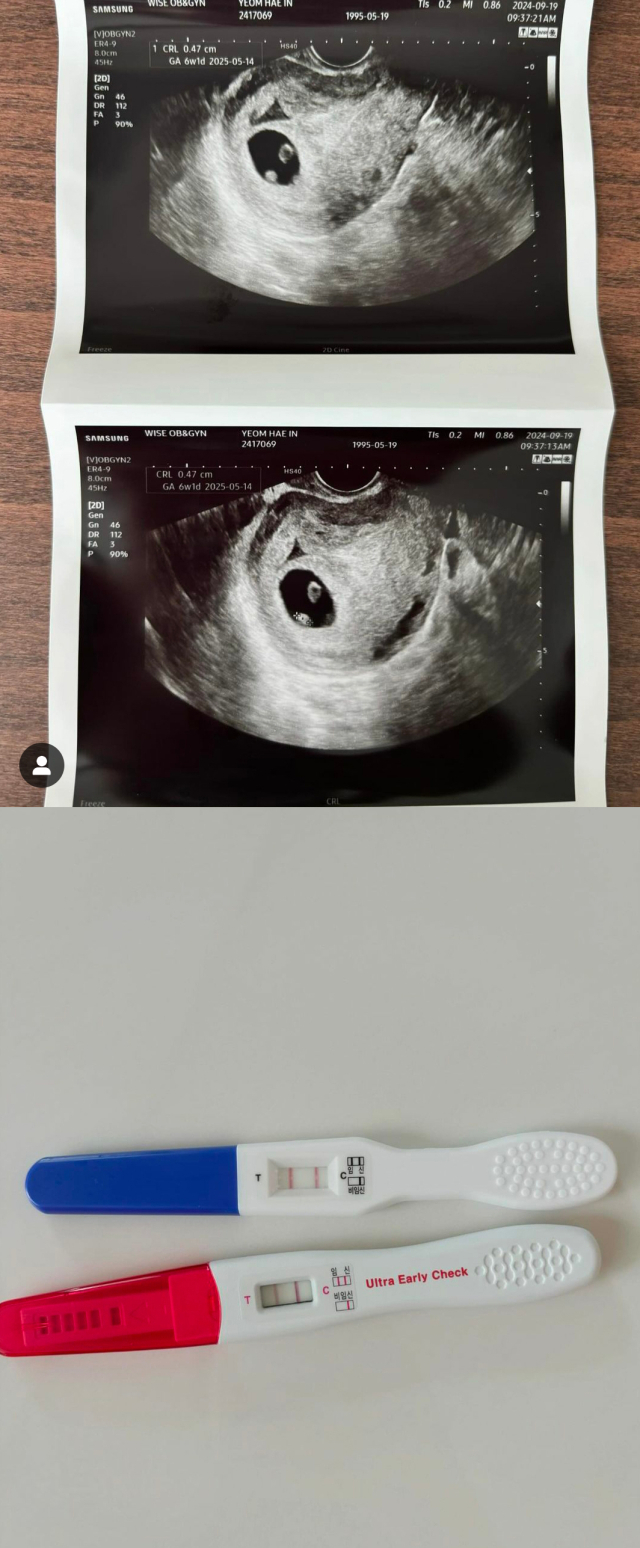

해인은 지난 19일 자신의 개인 소셜미디어 계정을 통해 "네…… 둘째에요…"라는 글과 함께 초음파 사진과 두 줄이 선명한 임신테스터기 사진을 업로드 했다.

그러면서 해인은 "처음부터 둘째까지 계획했지만 생각보다 빠르게 찾아와준 우리 둘째... 태명을 지어줘야 하는데 태몽을 꾼 것도 없고... 어찌 이쁘게 지어줘야 할지 고민이네요 ㅎㅎ 지금도 지아 덕분에 너무 행복한데 앞으로는 둘째로 인해 더 큰 행복이 생길 거 같네요. 우리 둘째 6w1d ♥"이라고 설명했다.